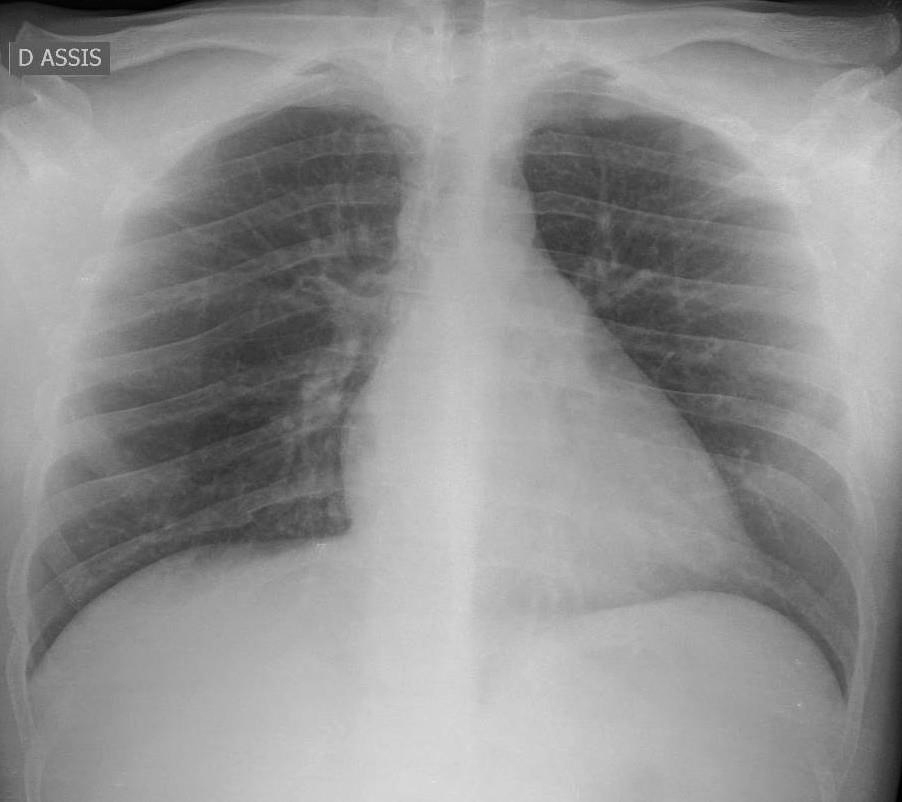

La radiographie de thorax est également utile dans ce contexte et peut orienter vers une sarcoïdose en cas d’adénopathies hilaires, ou vers une connectivite en cas de syndrome interstitiel (au premier rang desquels les poumons rhumatoïdes).

facteurs antinucléaires (FAN) positifs titre 1/320 ; anticorps anti-ADN natifs positifs = 214 UI/L (fortement positif) ; facteur rhumatoïde et anticorps anti-CCP négatifs ; électrophorèse des protides = absence d’anomalie ; sérologies VIH-VHC négatives ; sérologie VHB : antigène HBs négatif, anticorps anti-HBc positif, anticorps anti-HBs positif. Vous avez demandé une radiographie de thorax qui est la suivante :

Figure 1 (Source : Jeanne de La Rochefoucauld, La Revue du Praticien)